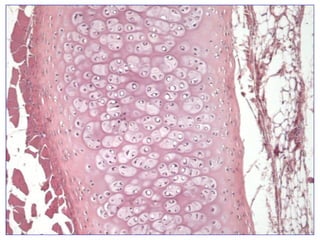

El documento describe diferentes aspectos de la histología del cartílago y el hueso, incluyendo las estructuras del cartílago como condroblastos, matriz y lagunas, y las estructuras óseas como conductos de Havers, osteoblastos y osteoclastos. También describe las etapas de la osificación endocondral, el proceso por el cual el cartílago se transforma en hueso, incluyendo las zonas de cartílago en reposo, proliferación, hipertrofia, erosión y osificación.